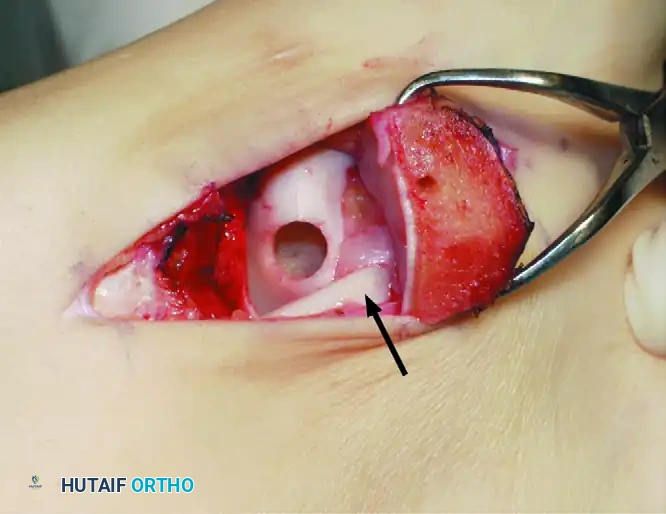

Step 1: Recipient Site Preparation

Once the lesion is fully exposed, utilize a commercially available recipient sizer to determine the exact diameter of the defect. Harvesters are typically available in sizes ranging from 5 to 11 mm (larger sizes are available for massive defects, though multiple overlapping plugs—the "snowman" technique—may be used).

Place the recipient harvester strictly perpendicular to the articular surface for dome lesions, or at a 45-degree angle for talar shoulder lesions.

Impact the tubular chisel to extract the recipient core to a precise depth of 10 mm. Remove the core, leaving a perfectly cylindrical defect. Drill multiple small holes into the subchondral bone at the base of the recipient hole to stimulate marrow bleeding and enhance graft integration.

Step 3: Graft Insertion and Seating

Bring the donor harvester containing the graft to the ankle. Align the harvester perfectly with the recipient socket.

Insert the cylindrical graft carefully into the recipient hole using the specially designed extruder or collared pin through the back of the donor harvester.

CRITICAL PITFALL: Do not remove the OATS harvester from the recipient site before the completion of full graft extrusion. Furthermore, do not allow the harvester to deviate from the insertion angle during extrusion. Either of these technical errors will place sheer stress on the graft and cause a catastrophic fracture of the donor core.

Once the graft is extruded into the socket, use the oversized sizer-tamp to gently tap the core until it is perfectly flush with the surrounding native cartilage. A proud graft will cause "kissing lesions" on the tibial plafond, while a sunken graft will fail to bear load, leading to fibrocartilage infill and cyst formation.